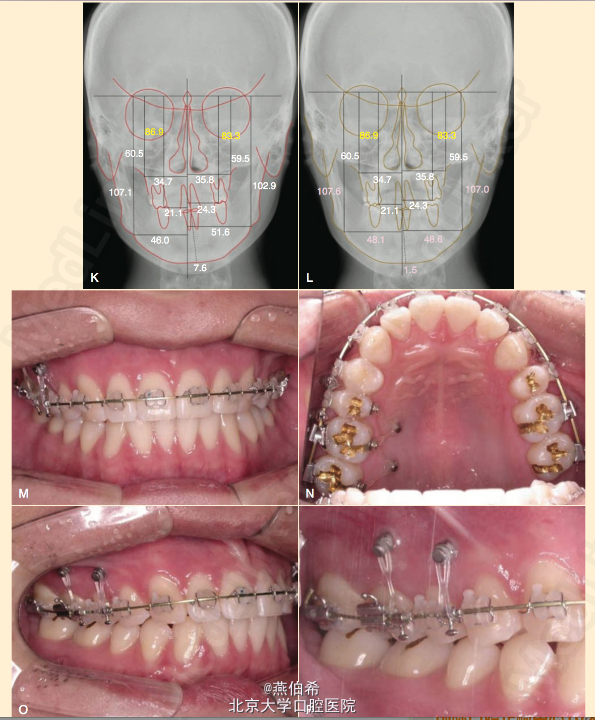

种植钉,矫正牙合平面倾斜及中线一例

OCT 5ed病例,22岁男性,正畸治疗术后,左侧TMJ疼痛弹响,牙合平面偏斜

最大牙尖交错位颏左偏,中线左偏。

压低及远中移动右上磨牙解决现有问题。